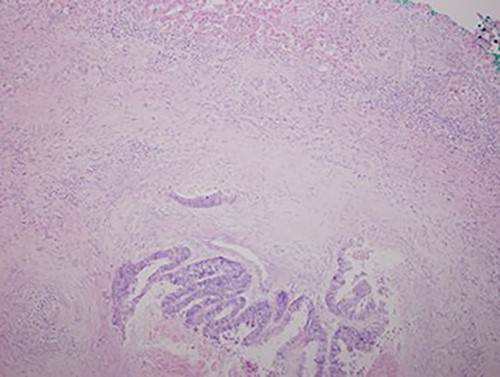

A chest X-ray at the time of admission showed right upper lobe mass (Fig. 1). Tru-Cut biopsy was performed and confirmed the diagnosis of non-small cell carcinoma (Figs 2 and 3). Multiple sections showed two nodules composed of well differentiated adenocarcinoma. The largest one measuring 4 mm from the resection margin, 2.5-cm away from hilar region and 5 mm from the outer surface. Smallest nodule was also composed of well-differentiated adenocarcinoma present 3 mm from the outer surface.

Low magnification power view of liver tissue with metastatic deposit from colon adenocarcinoma. (hematoxylin–eosin original magnification ×100).